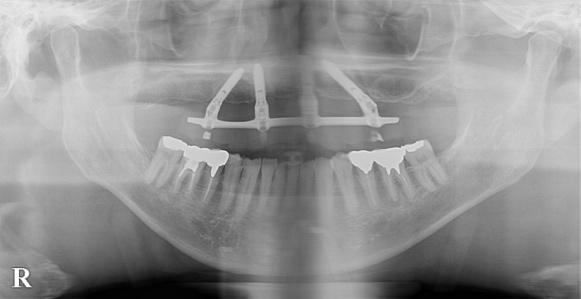

レントゲン写真撮影を行うと、右上1の歯根が吸収されてきている感じがあったので、過去に打撲などされたことがないか、お話を聞くと、小さな頃に転倒により右上1を脱臼され、再植処置を受けられたとのことです。

理想的な治療プランとしては、矯正治療を行い、唇側転位している右上1を正しい位置に整えてから、補綴物(歯の被せ物)を行うのですが、患者様の条件として海外に留学されるのでそれまでに治療を終了してほしいとのことと、矯正治療を行うと、右上1が抜けてしまう可能性がありました。

57歳、男性の方で主訴としては下の歯の銀歯が目立つので白い歯に変えてほしいとのことでした。元々は左下6の歯の根の方に病巣があり、そこが炎症を起こして激痛で来院されたのがきっかけでした。

根管治療(歯の根の治療のこと)終了後に左下5および6、右下5および6の合計4本の銀歯を白い歯に交換していくこととなりました。(左右7の銀の詰め物は気にならないのでそのままにしておいてほしいとのことでした。)

まずは1本ずつ銀歯を外して、仮歯に置き換えていきました。仮歯に置き換えていくのは簡単そうに思うかもれないのですが、銀歯を力づくで外すと歯が割れてしまうかもしれないので、1本ずつ丁寧に慎重に外します。歯を削り直したりと色々とやっていかないといけないので、地味ですが、時間が掛かります。しかしここは歯を綺麗に入れるためにも大切な作業なので、時間を掛けてコツコツとしていきます。歯の色を合わせるためにもシェードテイキングを行いました。今回は奥歯とのこともあって、患者様はそこまで審美性を求められていなかったので、ジルコニアクラウンのハイグレードタイプ(中間タイプ、松竹梅で言うと「竹」に当たります。)を使用しました。